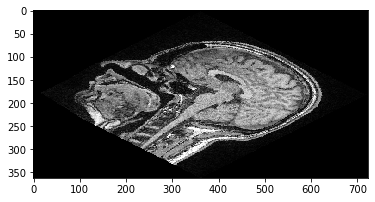

Para explicar un poco más la diferencia entre los sistemas de coordenadas, ahora usaremos una matriz de transformación afín para trasladar la imagen. La trasladaremos 100 píxeles en la dirección Y (sistema ZYX), también conocida como dimensión 1 (sistema 012) y -50 píxeles en la dirección X, también conocida como dimensión 2.

Traslación de imágenes usando clesperanto#

clesperanto sigue el sistema ZYX, y las matrices de transformación afín se escriben típicamente de la siguiente forma. Ten en cuenta que en el llamado sistema ZYX, el vector de traslación se lee x-y-z de arriba a abajo.

matrix = np.asarray([

[1, 0, 0, tx],

[0, 1, 0, ty],

[0, 0, 1, tz],

[0, 0, 0, 1],

])

cle_transformed = cle.affine_transform(image, transform=matrix)

cle.imshow(cle_transformed[100])